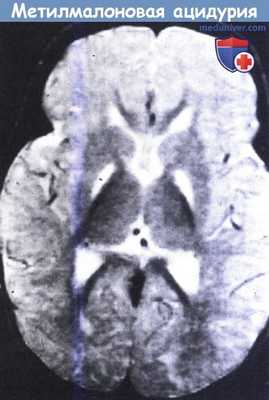

Метилмалоновая ацидурия.

На МРТ в Т2-режиме видны симметричные участки усиления сигнала в области бледного шара у восьмимесячного ребенка.

Также отмечаются признаки отсроченной миелинизации.